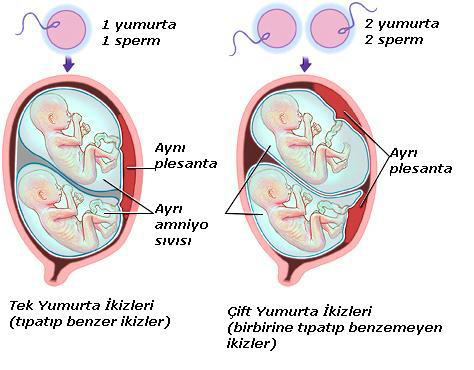

İkiz gebelik veya çoğul gebelik rahim içinde birden fazla bebeğin aynı anda büyümesi demektir. 2 tane varsa ikiz diyoruz, 3 tane varsa üçüz diyoruz, genel adı ise çoğul gebelik deniliyor. Hemen burada kavram kargaşası yaşanmaması için tekil gebelik tekiz gebelik olarak geçiyor tıp dilinde. İkiz gebelikler nasıl oluşur, adet dönemimde bir den fazla yumurtanın döllenmesi ve ayrı ayrı rahim içinde gelişmeye başlamasıyla buna çift yumurta ikizi deniyor. Veya döllenen bir yumurtanın döllendikten sonra içinde bölünmesine sonucuyla oluşmasına çoğul gebelik oluşuyor buna da tek yumurta ikizi deniyor. Çift yumurta ikizi ve tek yumurta ikizi deyimi buradan geliyor, çift yumurta ikizi birden fazla yumurtanın üç yumurta ikizi de olabilir tabi ki ayrı ayrı spermler tarafından döllenmesi ve rahim içine yerleşmesidir.

Tek yumurta ikizi de tek baştan oluşan bir yumurtanın döllendikten sonra ayrılmasıdır. Normalde yumurtaya tek bir sperm girerek döllenme olayını gerçekleştirir. Yumurtanın içine sperm girdiği anda yumurtanın tarafı kalın bir zarla çevrilerek başka sper rflln yumurtaya girmesi önlenir. Ancak bazı durumlarda iki yumurta aynı anda olgunlaşarak serbest bırakılır. Bu durumda iki farklı sperm iki farklı yumurtayı döllemiş olur. Bunun sonucunda ayrı yumurta ikizleri meydana gelir. Bunların genetik yapıları birbirinden farklıdır. Cinsiyetleri aynı olabileceği gibi farklı da olabilir. Birbirlerine ancak farklı zamanda doğmuş kardeşler kadar benzerler.Döllenen tek yumurtanın ikiye ayrılarak, ayrı ayrı canlılar oluşturması sonucunda ise tek yumurta ikizi meydana gelir. Tek yumurta ikizlerinin genetik yapısı birbirleriyle tamamen aynıdır. Buna bağlı olarak cinsiyetleri, yüz şekilleri, saç renkleri, göz renkleri, kan grupları gibi genetik özellikleri de aynıdır.